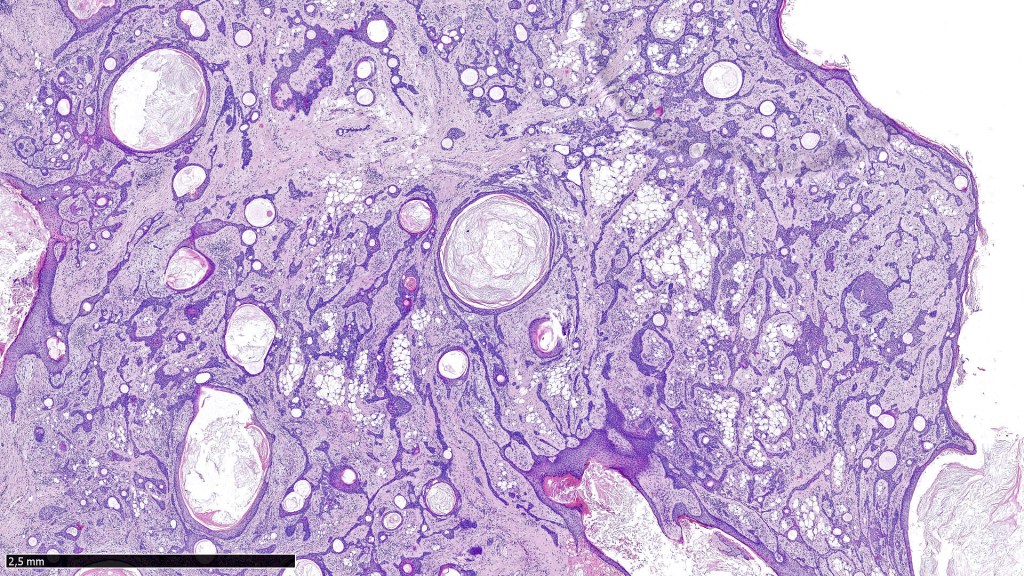

•Well circumscribed unencapsulated, nodular/multinodular silhouette composed of an admixture of epithelial & mesenchymal elements

•Often intensely basophilic due to mucinous deposits

•Keratocysts & squamous foci

•Stromal sclerosis & hyalinization

•Myxoid change

•Chondroid foci

•Fat (lipomatous mixed tumor)

•Calcification & osteoid